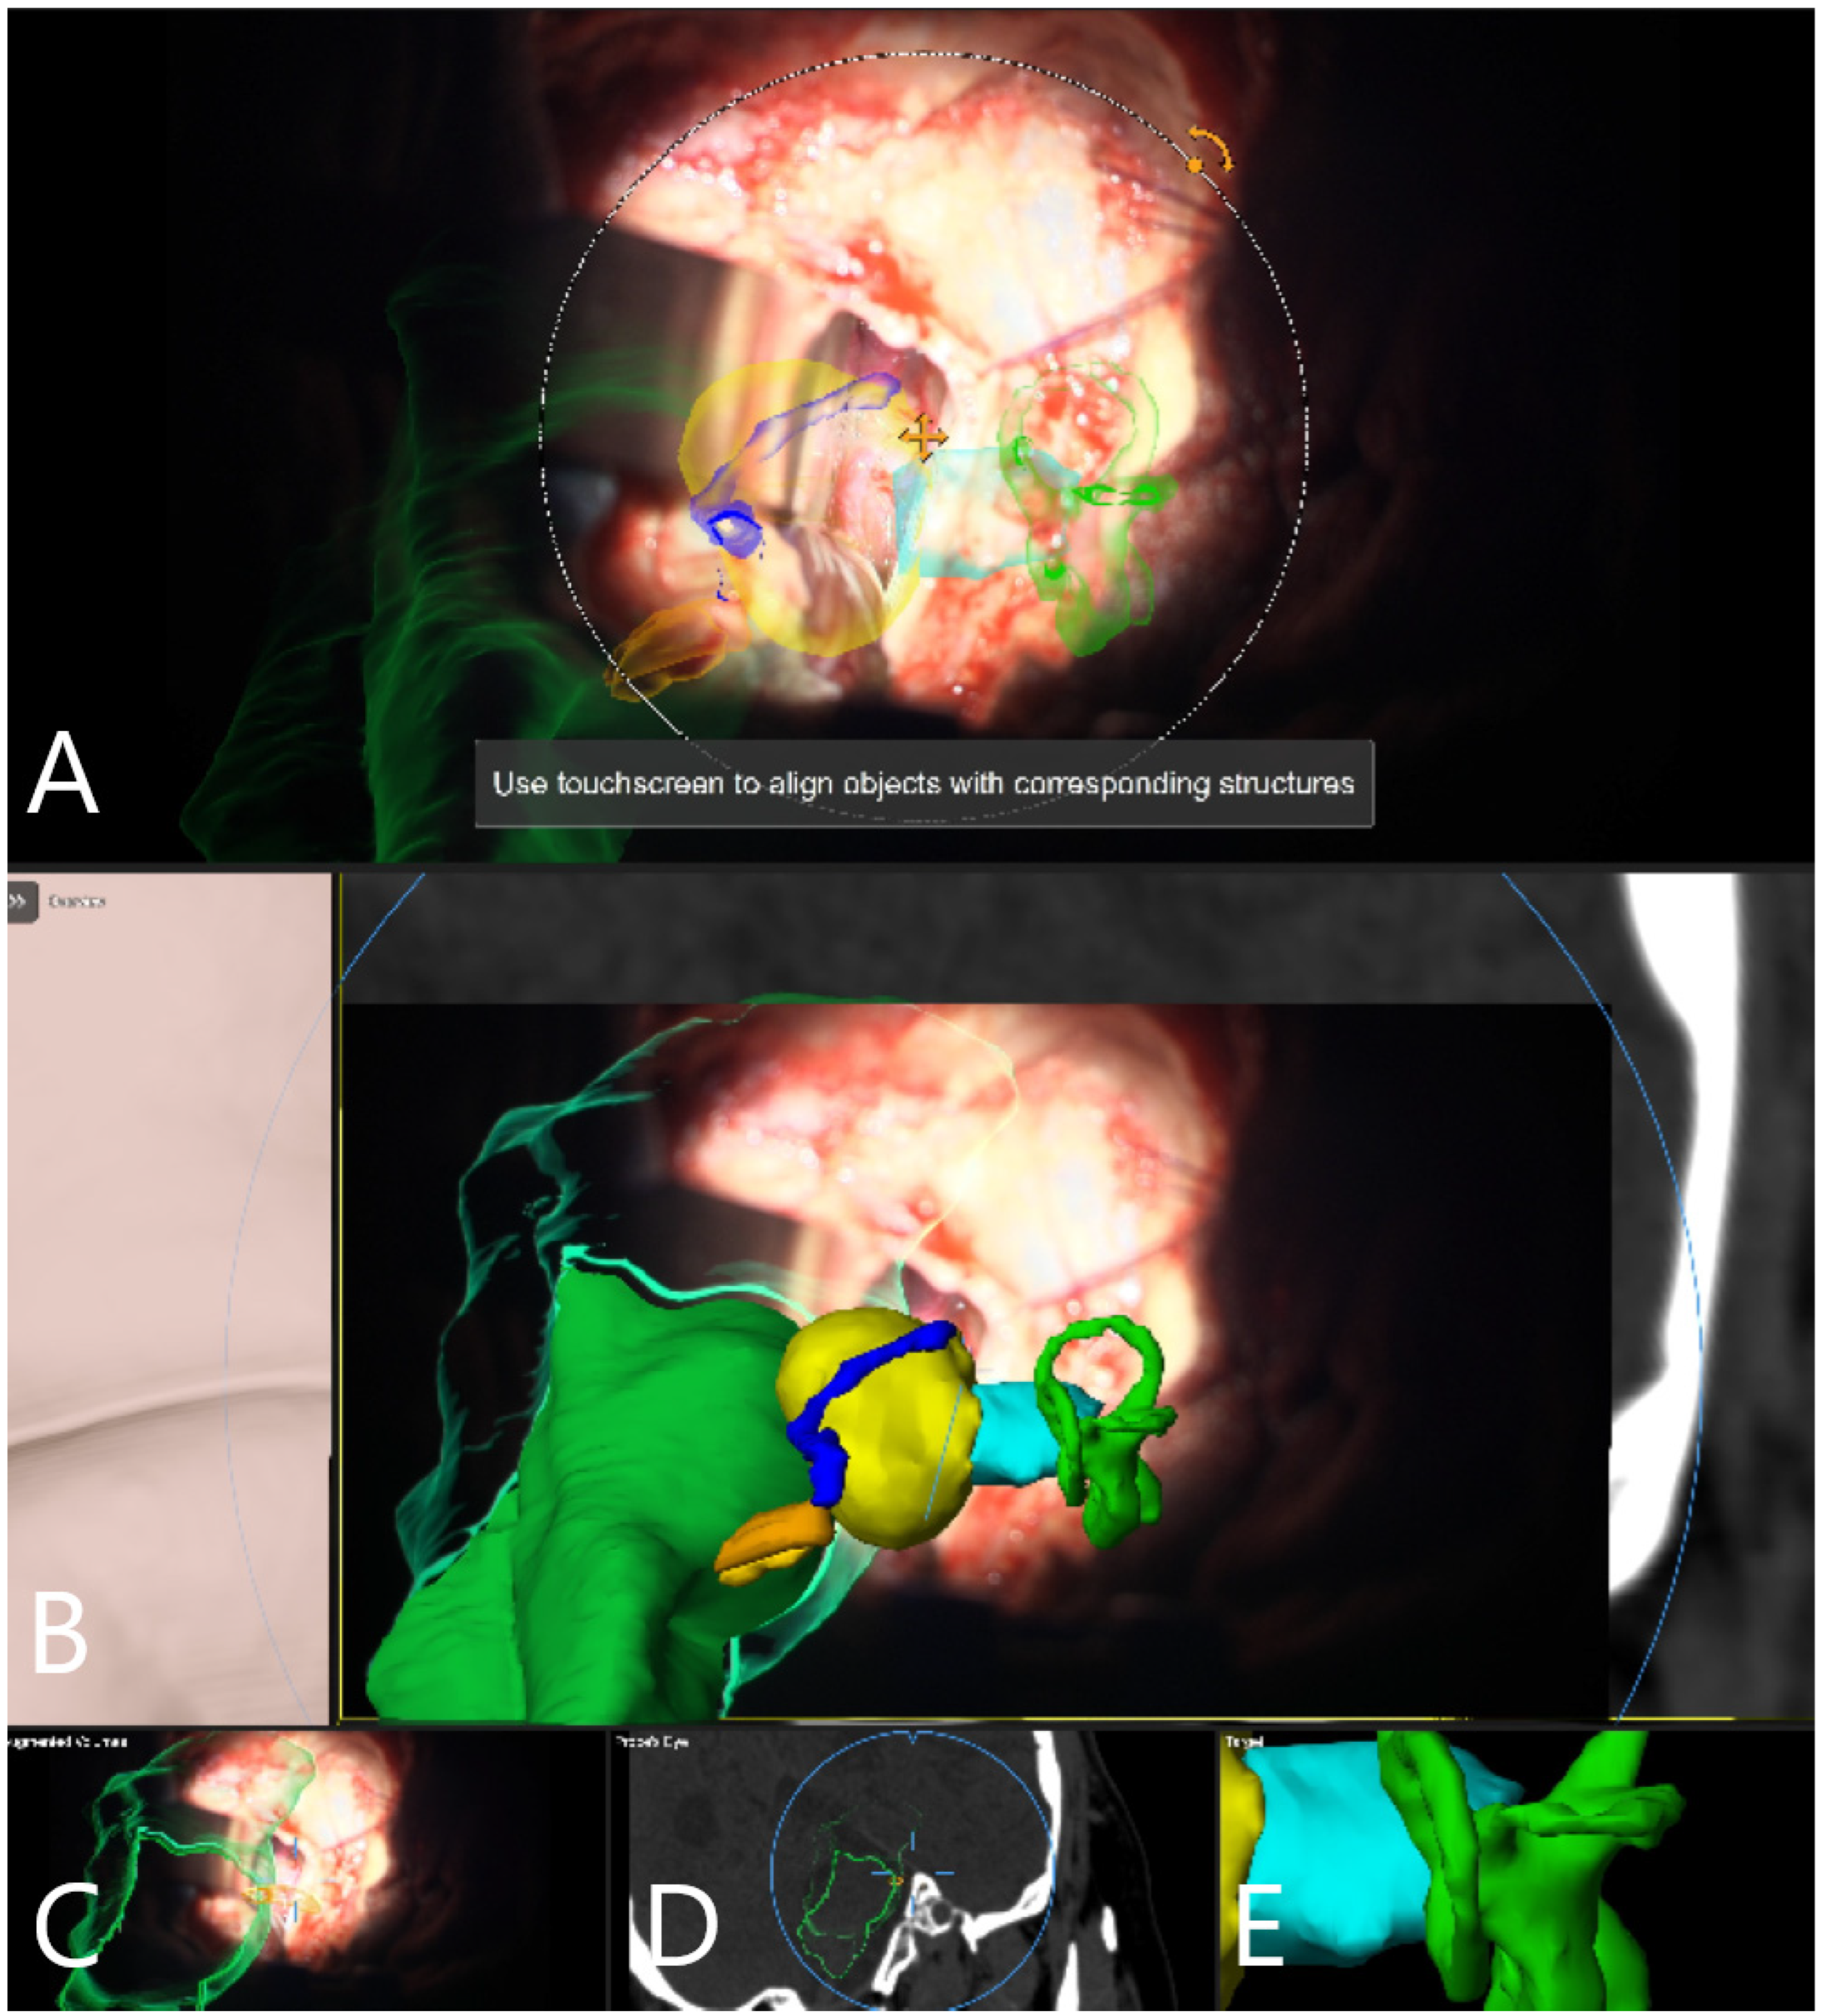

Illustrative Cases